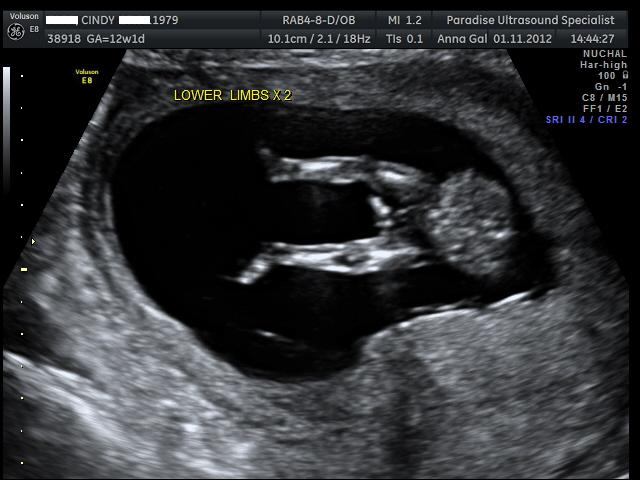

Here are the pics from my NT scan, the tech had a guess she said she is 70% positive the sex is.... can you guess? UPDATE - It's a boy :)